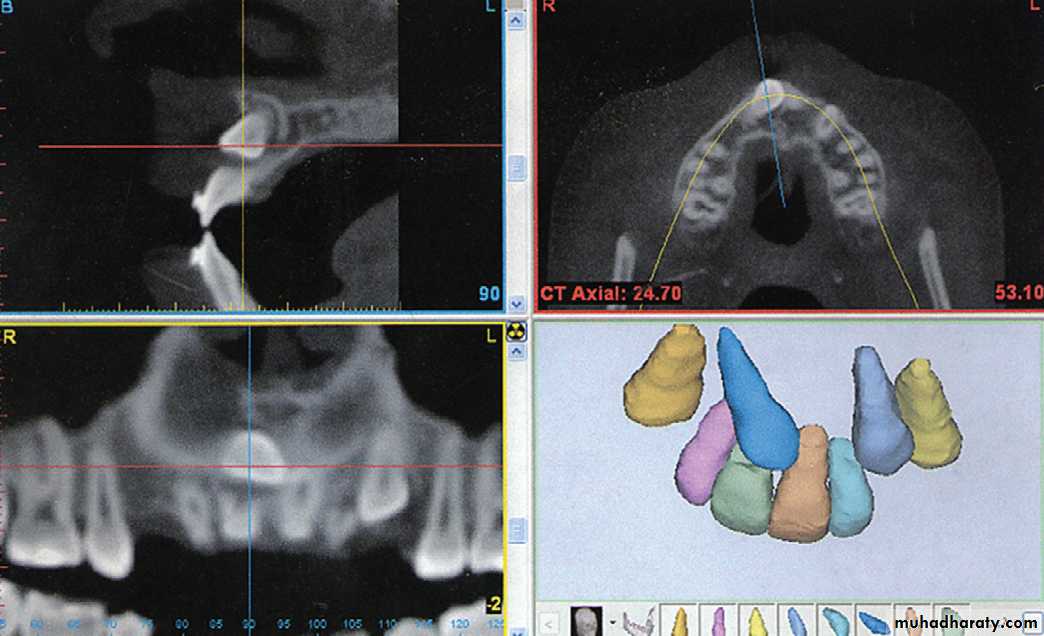

computed tomography

Three-dimensional images created by computed tomography (CT) have been used in medicine for many years now but were not used in evaluating orthodontic patients until recently for two reasons: the radiation dose and the cost.

• Cone Beam Computed Tomography.

• Cone beam computed tomography (CBCT) produces three dimensional volumetric images that can be reliably measured. A major advantage of CBCT imaging is that all extraneous structures that would otherwise obscure the desired view can be excluded. This allows visualization of dimensions for the wanted structures.